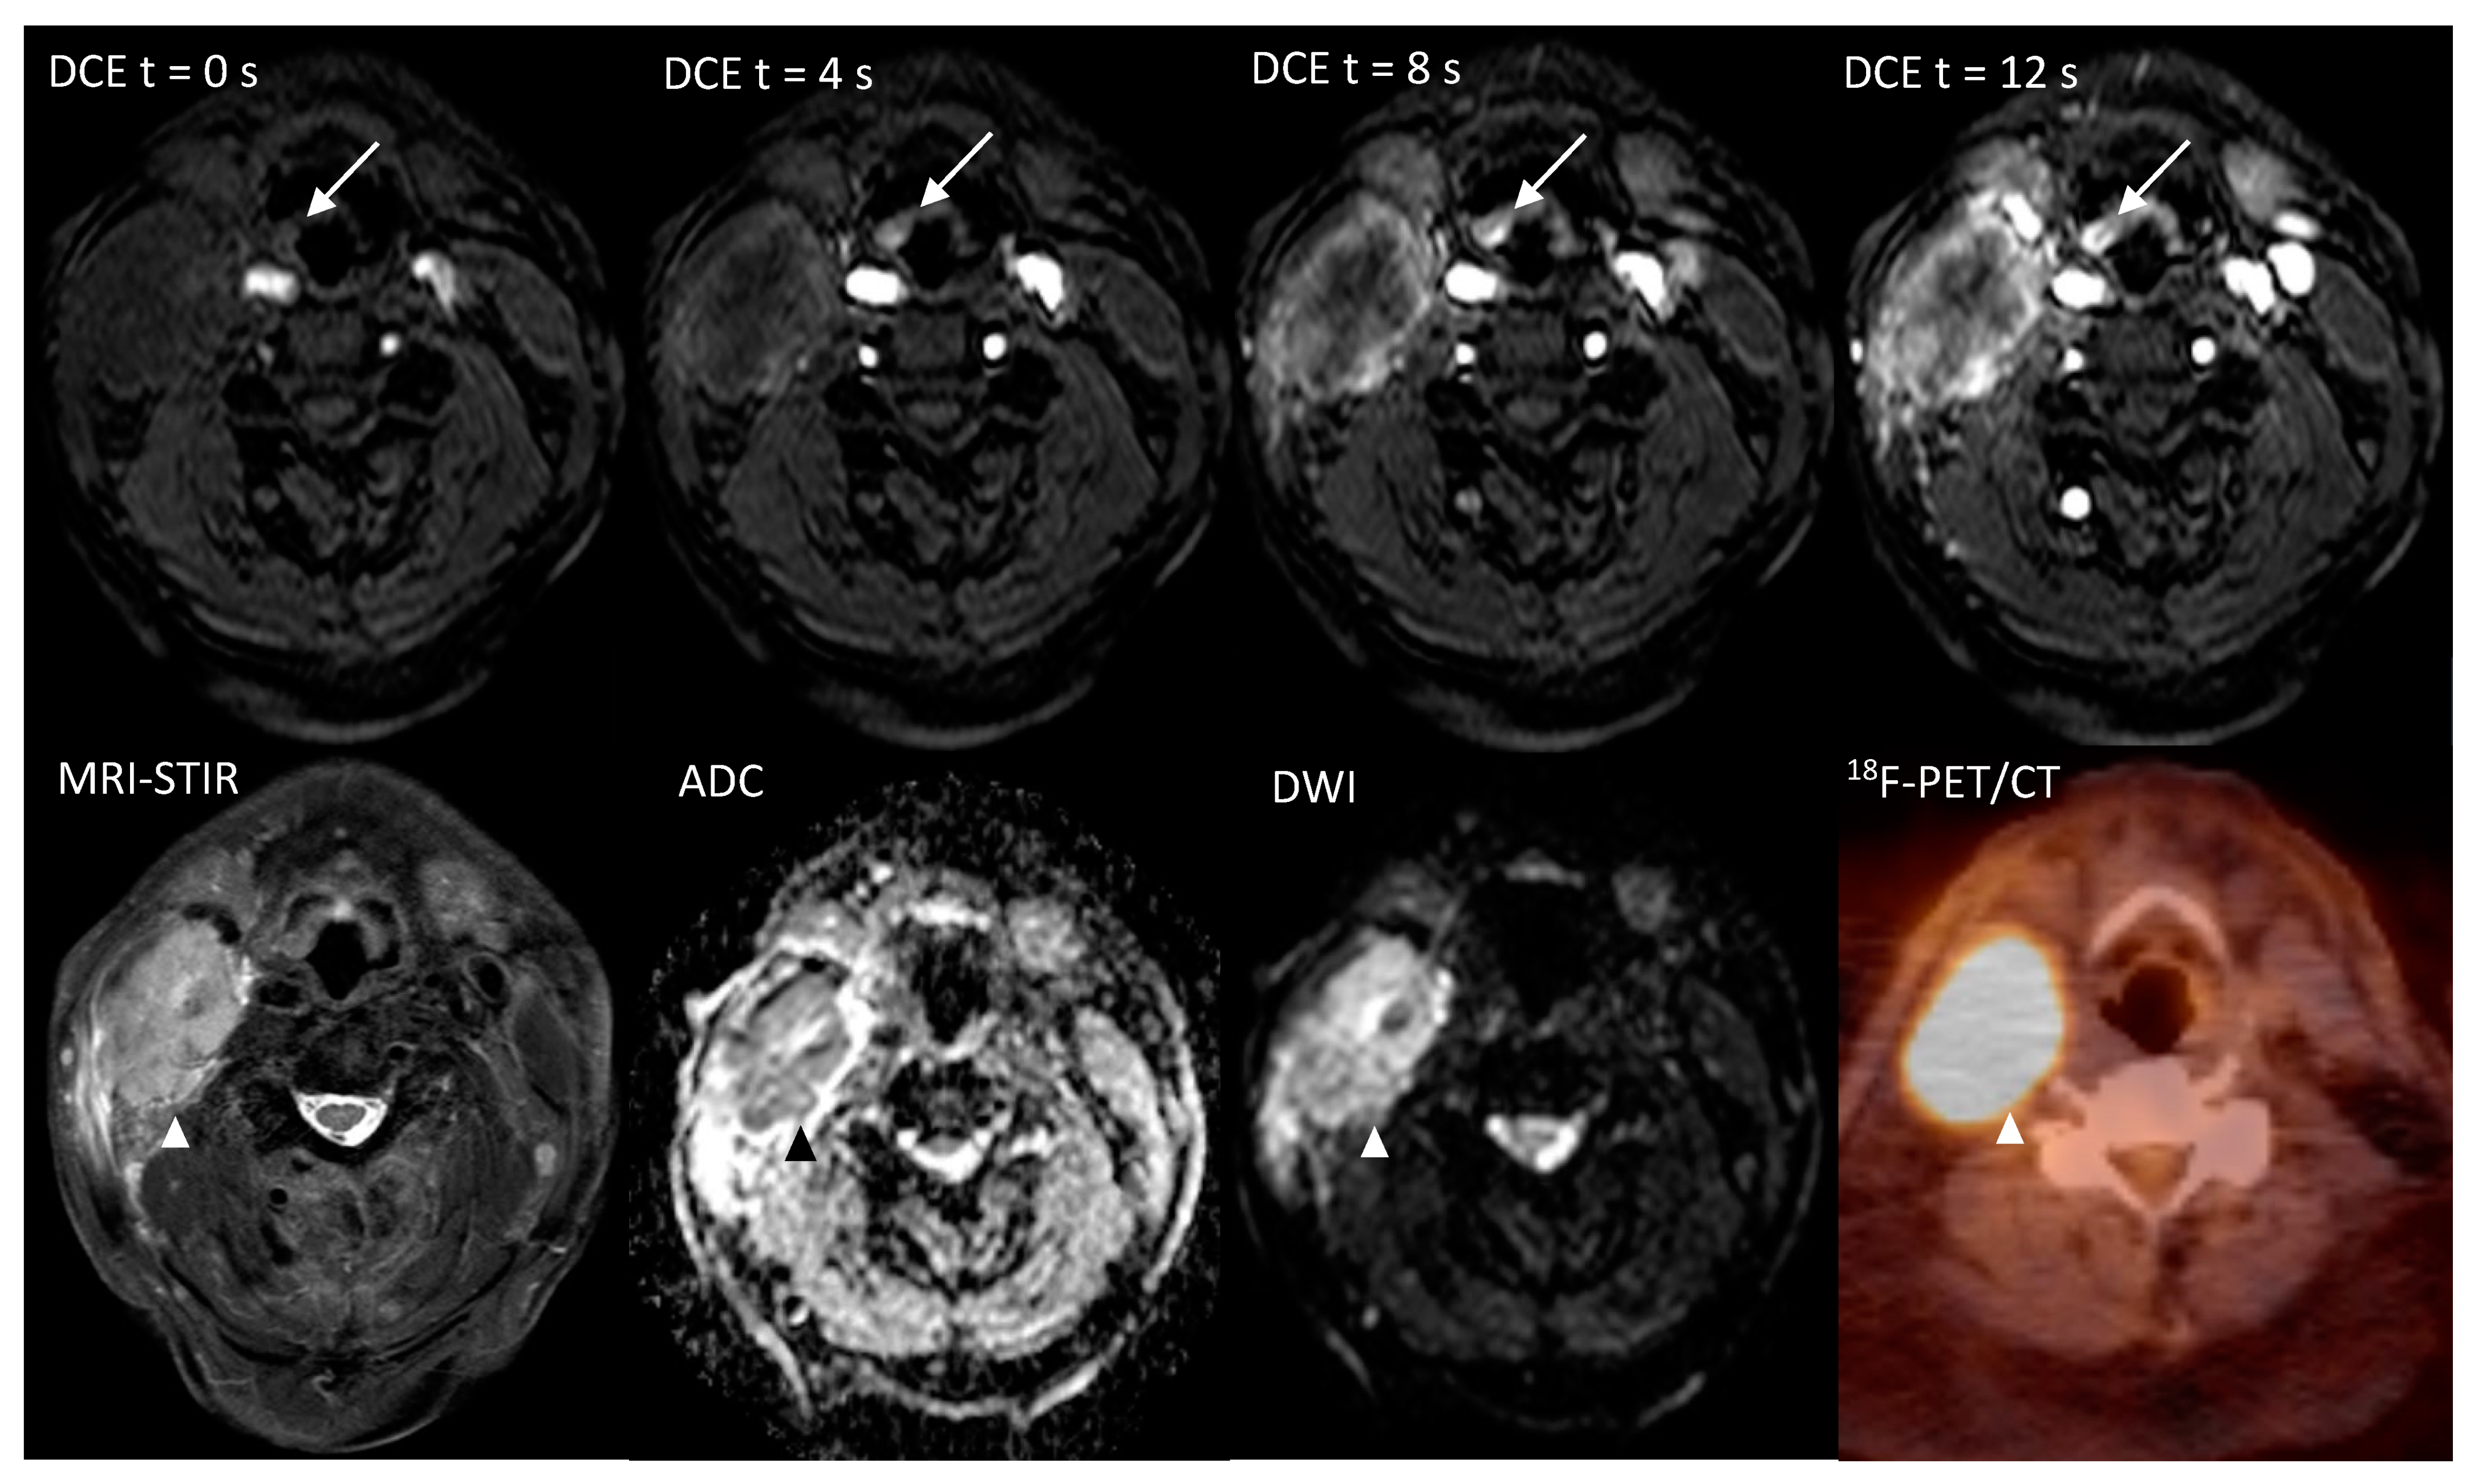

The per-patient analysis of (Table 4; II and III) with an independent positive read in either one of the combined modalities, resulted in a sensitivity of 100% for either DWI, ultrafast-DCE or PET and for either DWI or PET. In this analysis, an 11.1% (95%CI = 0.3–48.3%, p = 1.0) specificity was found for either DWI or DCE, either DWI or PET and for either DWI, DCE or PET. In one patient (5%), ultrafast-DCE provided decisive score when DWI and PET were scored as benign (Table 2; patient 19; Figure 1). In two patients (10%) ultrafast-DCE provided additional confidence to DWI for scoring probably malign lesion as malign (patient 5, 24).

Figure 1.

Imaging of a 71-year-old patient, with a hypopharyngeal (epiglottal) primary tumor detected only on the ultrafast-DCE imaging (arrow), whereas DWI and 18F-FDG-PET/CT did not detect the lesion. The overt malignant lymph node metastasis is marked with an arrowhead (Δ).

The additional value of ultrafast-DCE over DWI and 18F-FDG-PET/CT is that it might capture complementary unique tumor characteristics. Although the precise physiological explanation of enhancement on DCE remains ambiguous (e.g., angiogenesis and increased microvessel density) [19], early intensity changes were indicative for malignancy (Figure 2). This is in line with studies in breast cancer with an earlier time of arrival of contrast bolus in the malignant lesion [15,16,17]. Although the thin mucosal hypervascular layer and normal tonsillar tissue might interfere with the detection UPT, no other hypervascular lesions are generally present in the head and neck area. This could provide additional value for UPT detection by adding detection based on lesion vascularity, to DWI as a sign of tissue cellular density and 18F-FDG-PET/CT as a sign of tumor metabolism. Due to the limited spatial resolution of 18F-FDG-PET/CT for detecting small primary lesions, the addition of ultrafast-DCE may provide more confidence for the radiologist to mark a suspicious lesion as being malignant or benign (Figure 1, Figures S2 and S3) or when DWI and 18F-FDG-PET/CT are inconclusive. Furthermore, a similar high, positive agreement was found for ultrafast-DCE (77.6%) compared to DWI (76.6%) and 18F-FDG-PET/CT (71%), although more experience is gained with DWI and 18F-FDG-PET/CT. Also, the addition of ultrafast-DCE might enhance demarcation of tumoral boundaries, in order to optimize radiotherapy.

MR images were assessed by two radiologists (P.d.G., J.A.C.), with 13 and 33 years of experience with head and neck radiology, respectively. During the first reading session conventional MRI sequences (T1w, T2w, STIR) were allowed to be used combined with DWI. Asymmetrical lesions with a higher signal intensity on DWI (high b1000) and a low ADC were assigned as being potentially malignant. A second MR reading session after a 2 months’ time-interval (to limit recall bias) was performed using conventional MRI sequences combined with ultrafast-DCE. Moreover, a very early contrast enhancement on ultrafast-DCE (Figure 1) and distortion of normal anatomy were considered signs of malignancy.